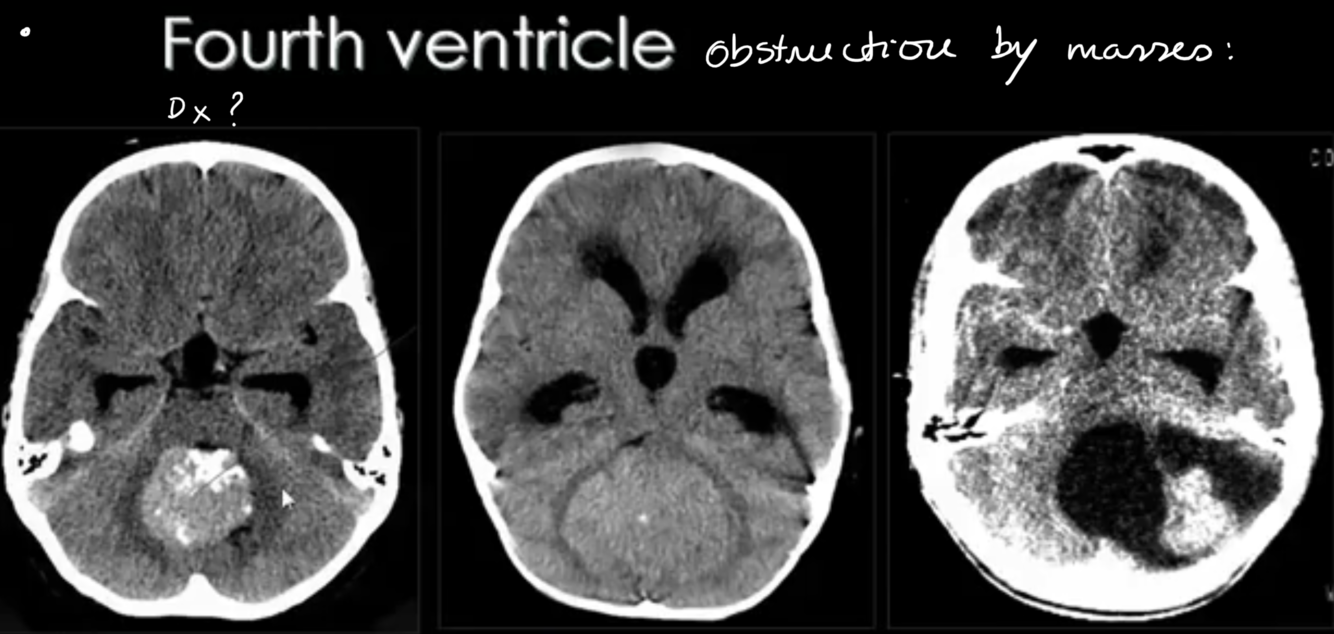

4TH VENT OBSTRUCTION:

-causes?